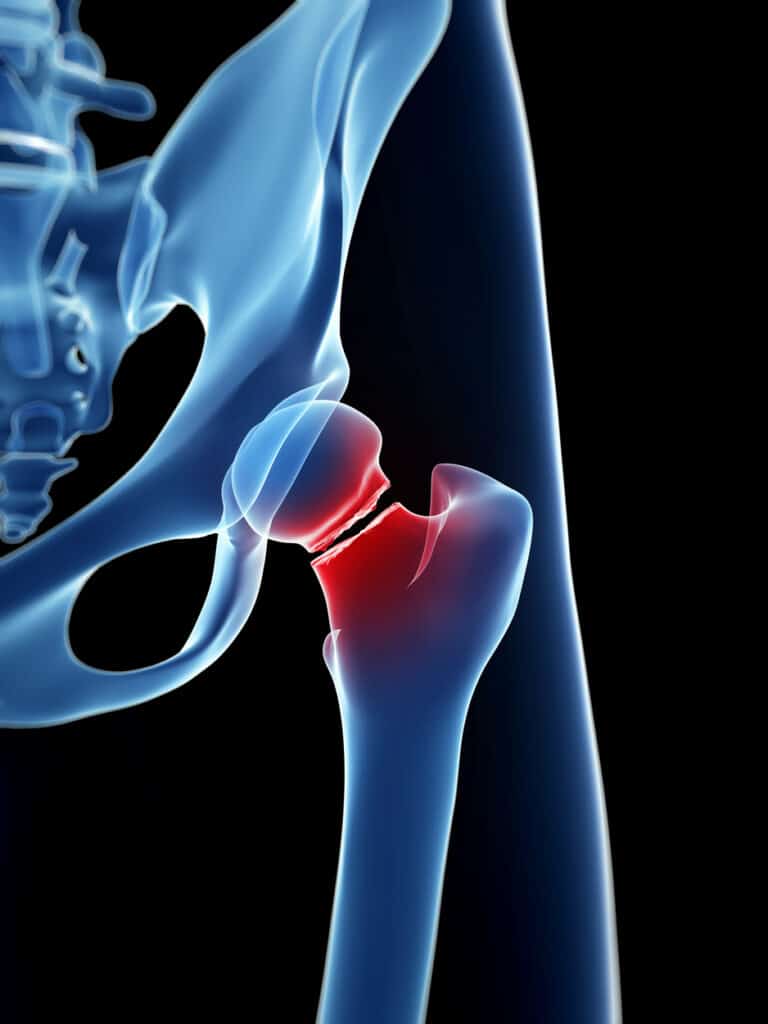

Hip pain may be caused by arthritis or injuries. Our specialists offer treatments to relieve pain and restore mobility.